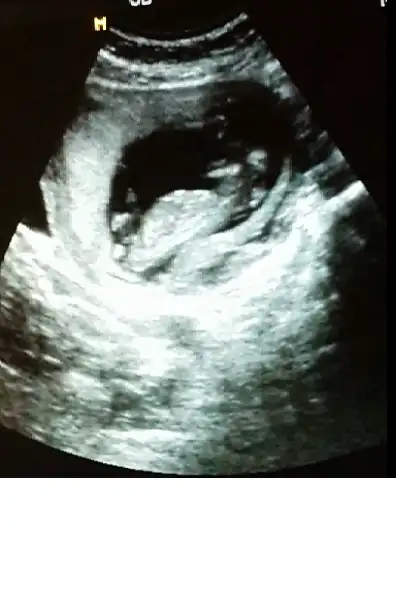

kızlar cinsiyet tahmini yapabilen var mı :)

Gijnij merhaba ben seni ve buranin sıkı takipcilerindenim benim de 2 kizim var ALLAH nasip ederse 3 cuye hamileyim 14 haftalik rica etsem resimi eklesem bana yorum edermisin image.webp

ben mesaj atmıştım sana ama sorun oldu gitmedi sanırım. bu fotoda ben nubu çözemedim canım